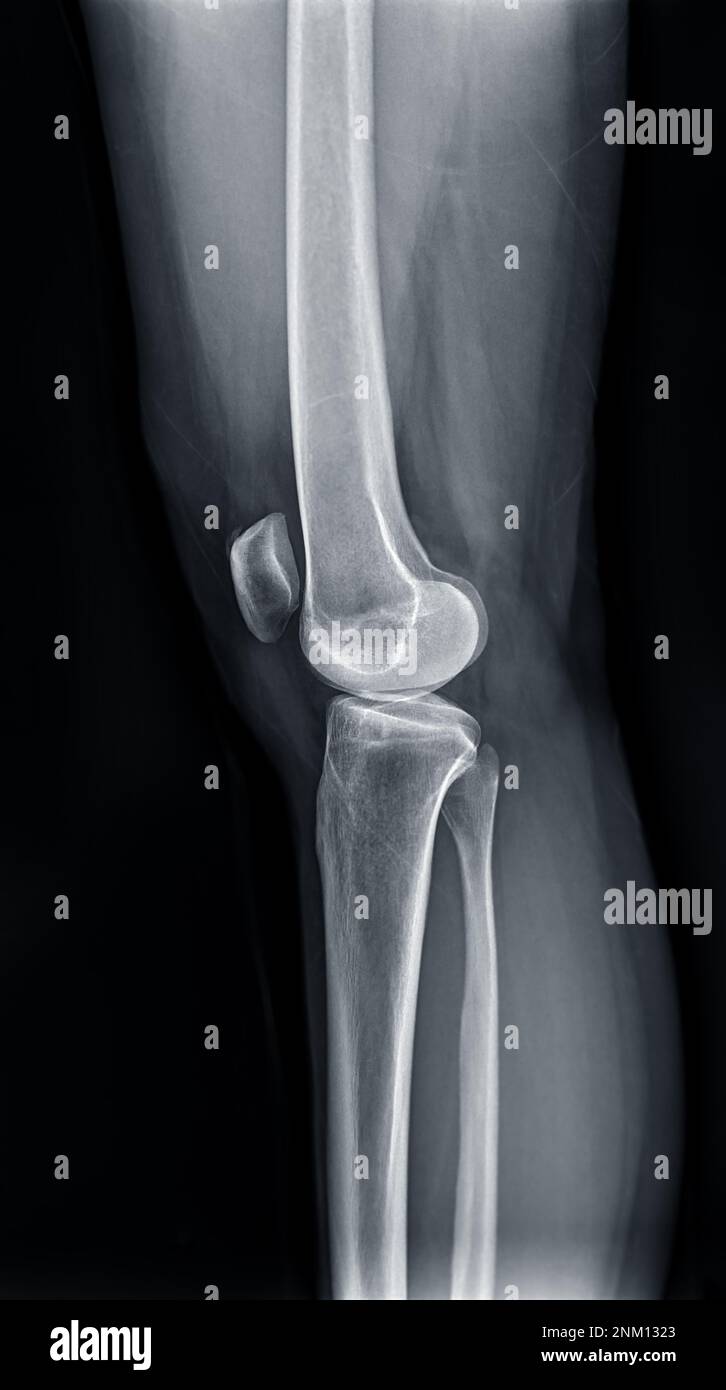

Radiografía de película de la articulación de la rodilla izquierda Cajones Y Bostezos En Rodilla La rodilla es la articulación más grande del esqueleto. Este documento resume varias maniobras clínicas utilizadas para explorar la rodilla, incluyendo pruebas para detectar derrame articular, condropatía rotuliana, inestabilidad de la. Se realiza con el paciente en. La exploración incluye inspección, palpación y pruebas de movilidad como el. Prueba especial utilizada para evaluación de ligamentos colaterales y estabilidad medial y. Cajones Y Bostezos En Rodilla.

RADIOGRAFÍA ANTEROPOSTERIOR y LATERAL RODILLA Blog de Fisioterapia Cajones Y Bostezos En Rodilla Prueba especial utilizada para evaluación de ligamentos colaterales y estabilidad medial y lateral. La rodilla es la articulación más grande del esqueleto. La exploración incluye inspección, palpación y pruebas de movilidad como el. Contiene los huesos fémur, tibia y rótula, así como meniscos y ligamentos cruzados anterior y posterior. Se realiza con el paciente en. En este video se muestra. Cajones Y Bostezos En Rodilla.